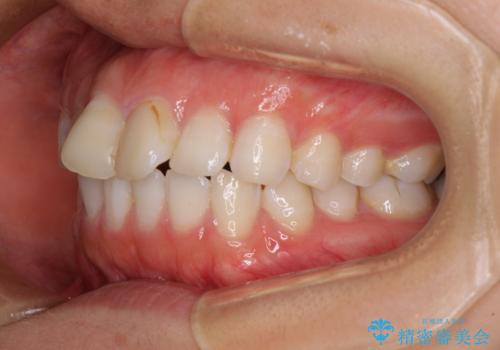

前歯の捻れを改善 インビザラインによる矯正治療

- 前歯の翼状捻転を気にして来院された患者様です。

全体的に叢生は軽度であったため、インビザラインにて矯正治療を行うこととしました。

前歯の幅の大きさも気になっていたため、IPRにより叢生を解消するとともに、歯の大きさも改善しました。